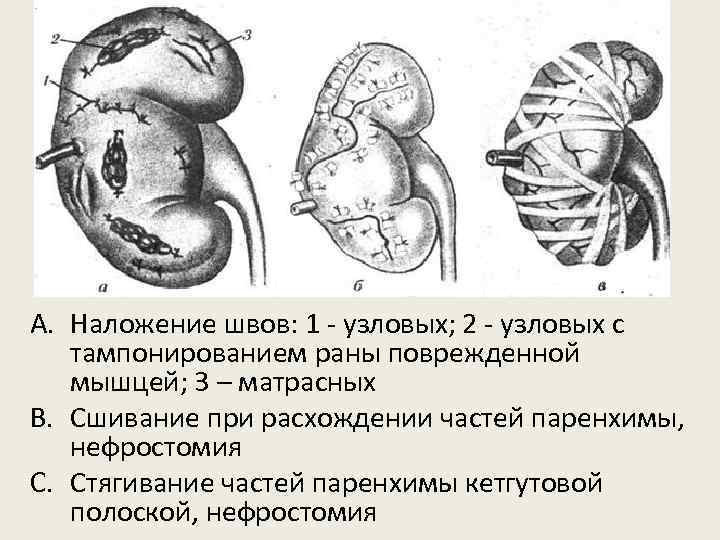

Хирургическая тактика • Раневую поверхность паренхимы почки закрывают жировой клетчаткой/мускульным лоскутком • В забрюшинное пространство через отдельный разрез вводят дренажную трубку и рану послойно зашивают • При небольших поверхностных разрывах почки капиллярное кровотечение останавливается без принятия кровоостанавливающих мер. • В случае диффузного капиллярного кровотечения из глубокой раны почки ее тампонируют кусочками травмированных мышц, ушивают узловыми или матрасными швами

A. Наложение швов: 1 - узловых; 2 - узловых с тампонированием раны поврежденной мышцей; 3 – матрасных B. Сшивание при расхождении частей паренхимы, нефростомия C. Стягивание частей паренхимы кетгутовой полоской, нефростомия

При раздавливании верхнего и нижнего концов почки выполняют ее резекцию A. Рассекание и отделение фиброзной капсулы почки B. Высекание верхнего почечного сегмента; C. Прошивка кровоточивых сосудов и ушивания стенки верхней чаши D. Ушивание паренхимы и фиброзной капсулы почки.